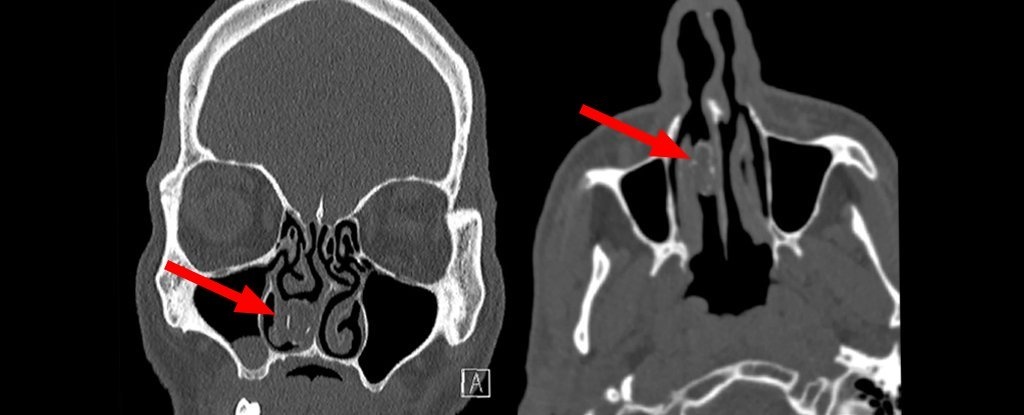

| Gói cần sa kẹt trong khoang mũi người đàn ông Australia. |

Khi quét vùng mũi, các bác sĩ phát hiện ra “một khối cứng màu xám” trong khoang mũi của người đàn ông. Các chuyên gia tai mũi họng tại Bệnh viện Westmead (Sydney) đã thực hiện nội soi gây mê để loại bỏ nó và lôi ra một “viên nang cao su có chứa rau/cây thoái hóa".

18 năm sau, ông giúp các bác sĩ tạo ra ca mổ đầu tiên trên thế giới để lấy một vật thể dài 1,9 cm từ khoang mũi với tên kỹ thuật là rhinolith (tiếng Hy Lạp nghĩa là đá mũi).